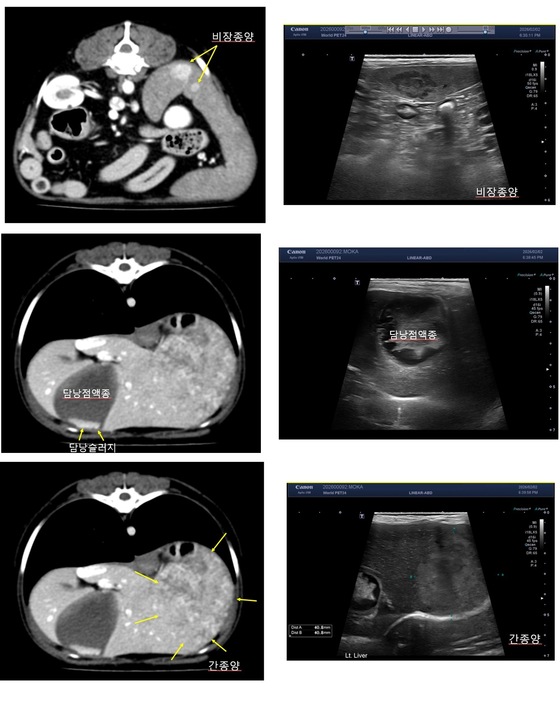

추가 정밀검사도 진행됐다. CT(컴퓨터 단층촬영)와 초음파, 방사선 검사 결과 담낭과 비장 이상 외에도 간에 종양성 병변이 의심되는 소견이 확인됐다. 단일 장기 질환이 아니라 복강 내 여러 장기를 함께 평가해야 하는 상황이었다.

14세 고령견에서 발견된 다발성 복강 내 장기 이상(월드펫동물메디컬센터 제공) © 뉴스1

의료진은 보호자와 충분한 상담 끝에 담낭 절제술과 비장 절제술, 그리고 간 조직 생검을 동시에 진행하기로 결정했다. 비장 종양의 경우 파열되면 급성 출혈로 이어질 수 있고 담낭 점액종 역시 파열 시 복막염으로 진행될 수 있기 때문이다.

이어 "14세와 같은 고령견에서는 코코처럼 복강 내 여러 장기에 이상이 동시에 나타나는 경우도 드물지 않다"며 "CT나 초음파 같은 영상검사를 통해 장기 상태를 정밀하게 확인하는 것이 치료 방향을 설정하는 데 중요한 역할을 한다"고 설명했다.